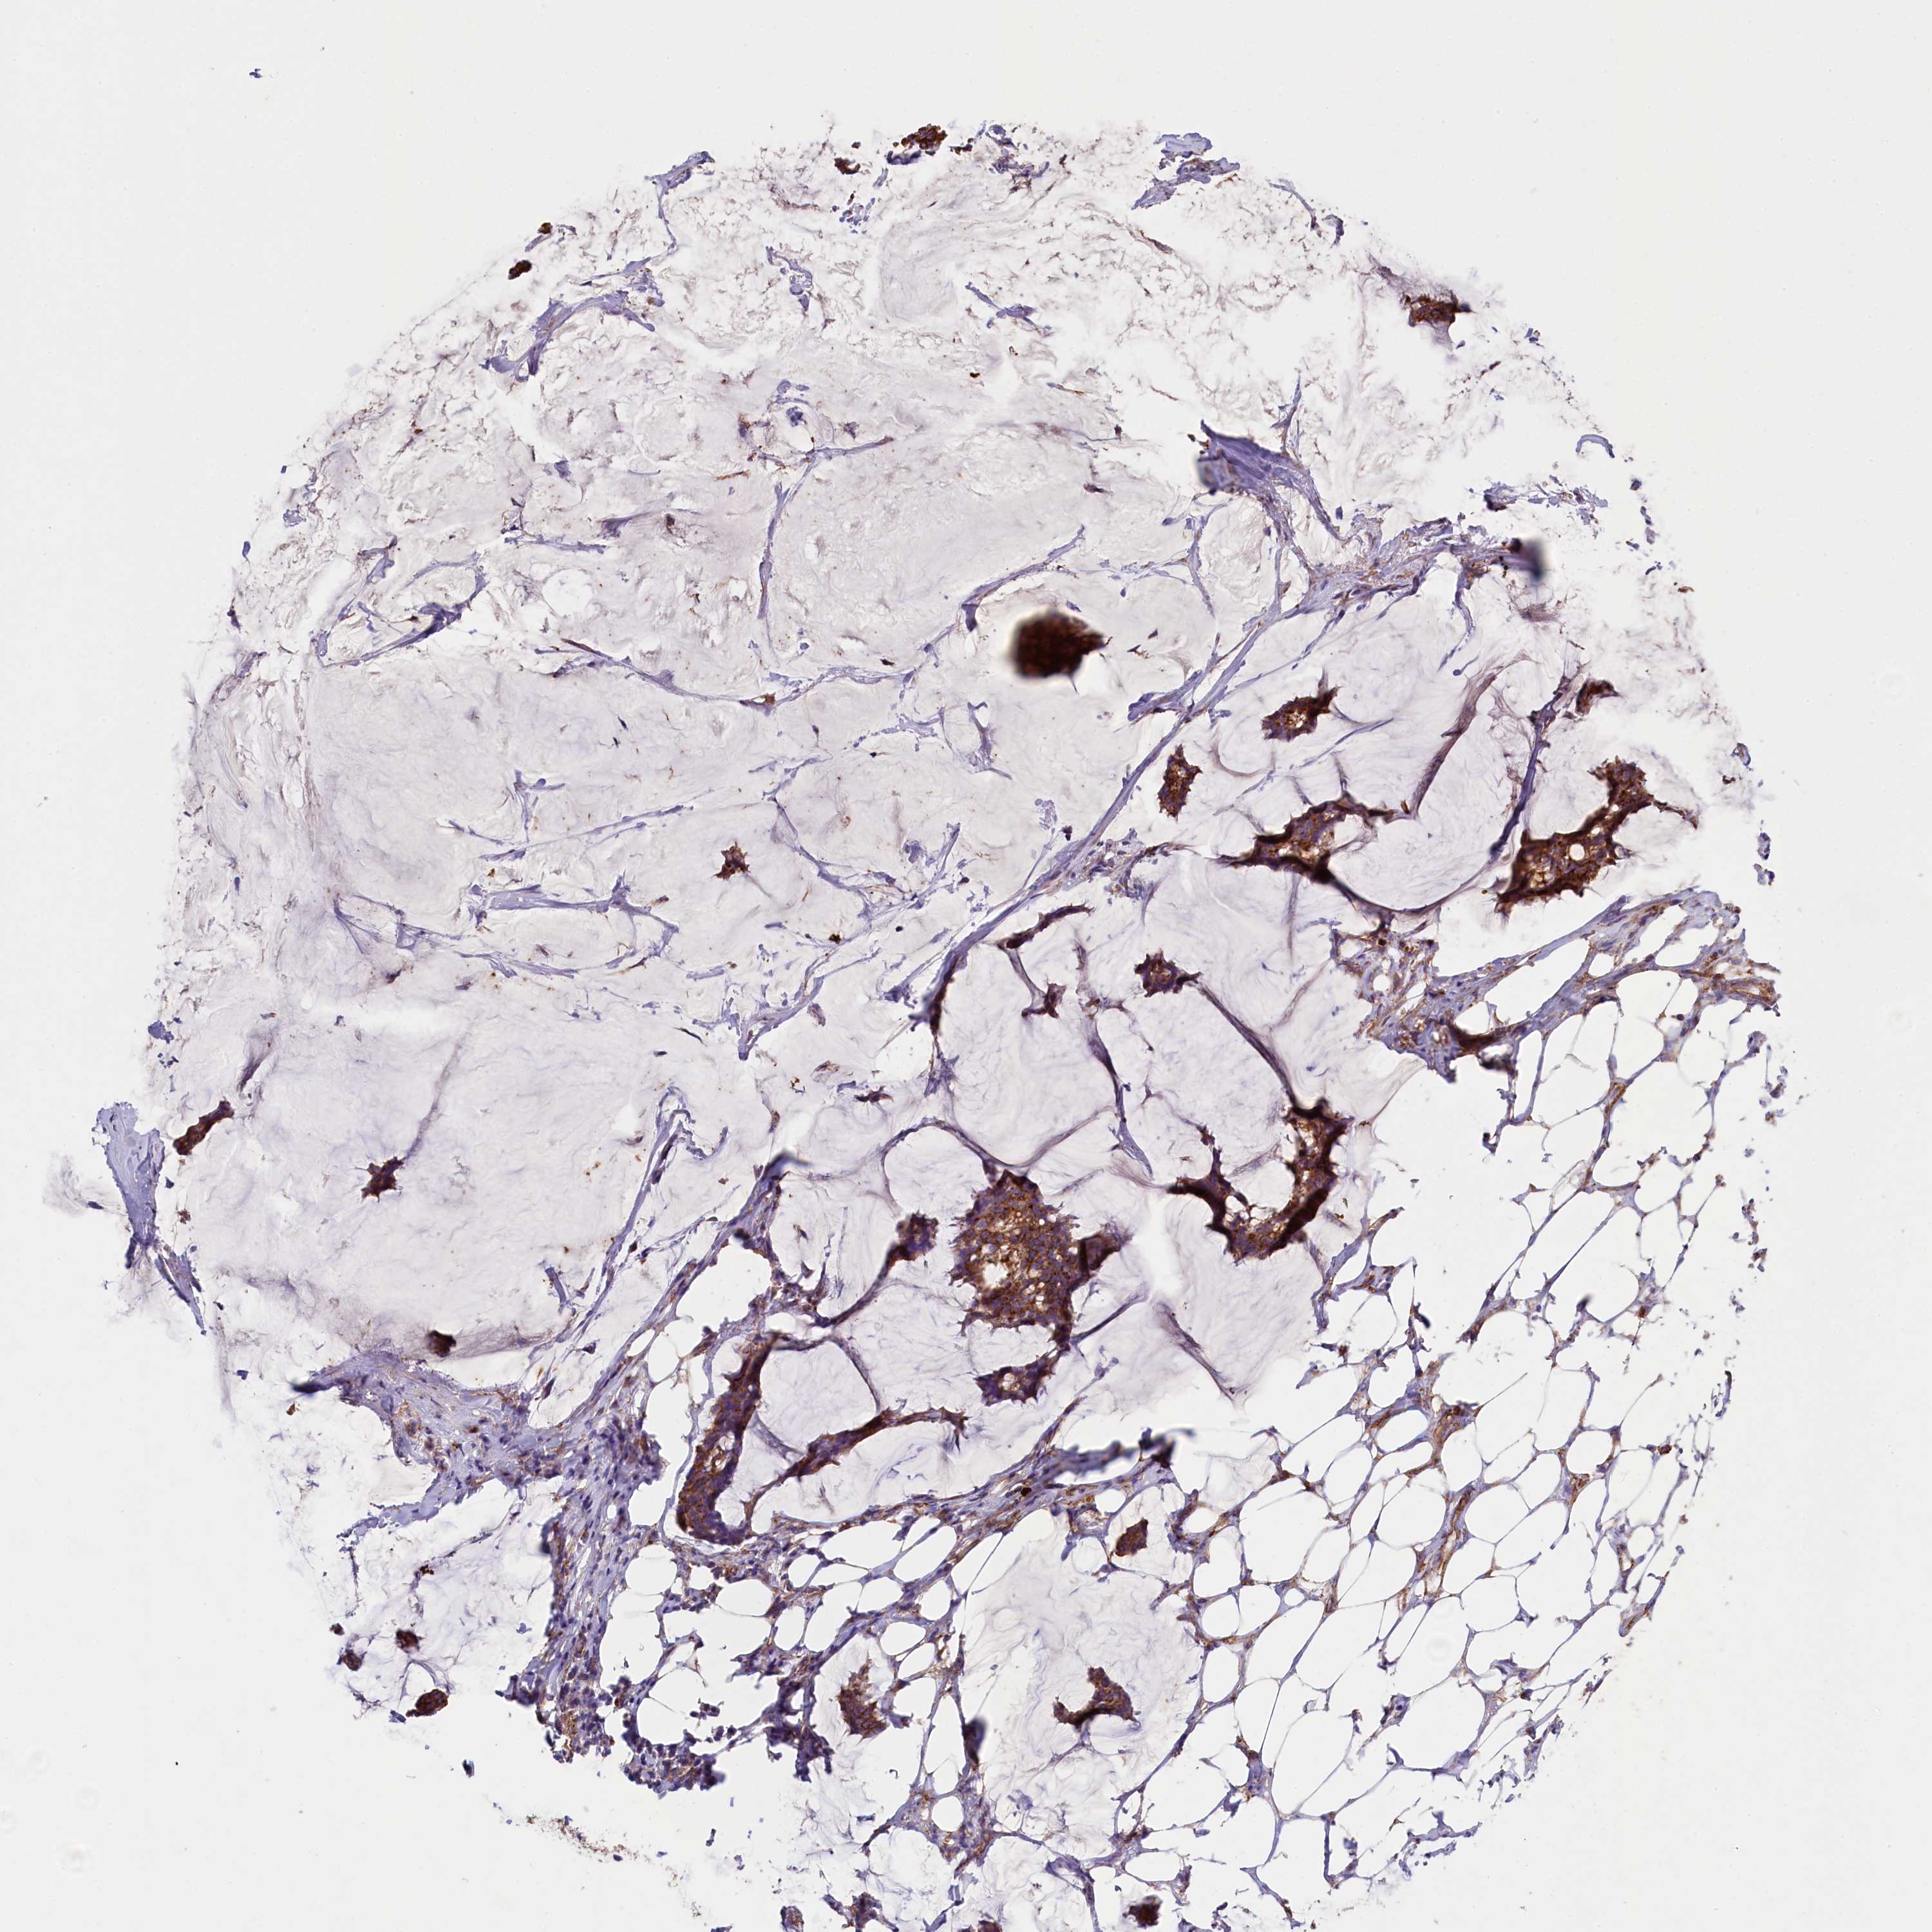

CANCER BREAST CANCER Show tissue menu

BRCA TCGA BRCA VALIDATION PROTEIN EXPRESSION